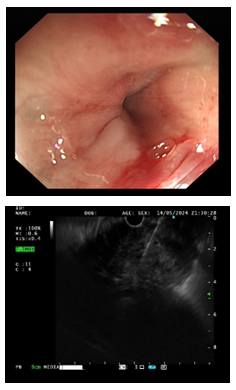

3.消化内镜中心完成首例超声内镜引导下细针穿刺活检术

5月8日, 驻疆专家史海涛成功完成新疆医院首例超声内镜引导下细针穿刺活检术(EUS-FNA),标志着新疆医院消化内镜诊疗技术迈上新台阶。